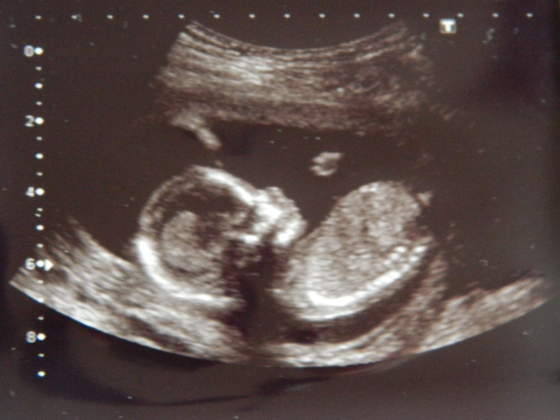

Kruszki, piękne zdjęciaA znacie płeć? Bo mi na dziewczynkę wygląda - tak po twarzy

hehehe no to zescie teraz napisalykruszki piękne małe słoneczko, a mnie na chłopczyka wyglądahihi

...w końcu dowiemy się wszystkie kto mieszka w naszych brzuchach... :-)